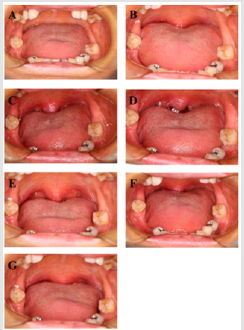

Figure 2: Typical clinical case treated by the Er:YAG laser. A, intraoral view of Pre. Tre. B, intraoral view of post 1st Tre. C, intraoral view of post 2nd Tre. D, intraoral view of post 3rd Tre. E, intraoral view of follow-up 3 m. F, intraoral view of follow-up 6 m. G, intraoral view of follow-up 12 m.

Typical clinical case is presented in Figure 2. The airway of the OSAHS patient was almost completely obstructed before the Er:YAG laser treatment (Figure 2A). After the 1st Tre., the base of uvula could be observed (Figure 2B). After the 2nd Tre., the whole uvula and palatoglossal arch showed up (Figure 2C). When the 3rd Tre. was completed, the uvula, palatoglossal arch, tonsil and even posteior pharyngeal wall were revealed (Figure 2D). Although the pharyngeal cavity narrowed gradually during the follow-up period, partial uvula and palatoglossal arch still showed up at end ((Figure 2E, F, G).